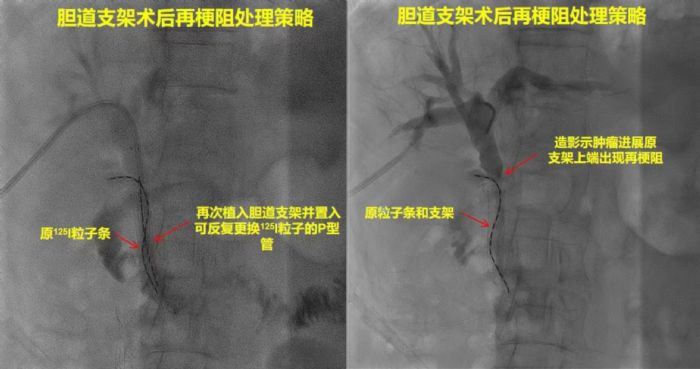

安徽省第二人民醫(yī)院肝膽外科專家金浩博士,長期從事肝膽胰外科疾病診治工作,他認(rèn)為惡性腫瘤行膽道支架治療的缺點(diǎn)是支架由于腫瘤生長導(dǎo)致再梗阻,125I粒子腔內(nèi)治療可有效彌補(bǔ),他們采用雙腔施源導(dǎo)管可控制腫瘤生長,半年后更換導(dǎo)管保證治療可延續(xù)性,已有相關(guān)文章發(fā)表。